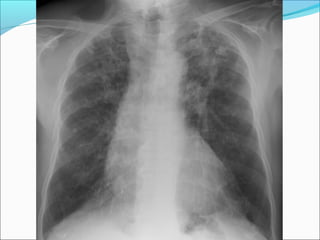

RADIOLOGY FINDINGS

Shows egg- shell hilar calcification and progressive

massive fibrosis. it also shows snow-storm appearance

in the lung fields.

 Emphysematous bullae are present in the upper

zones then later affect the lower lobes.